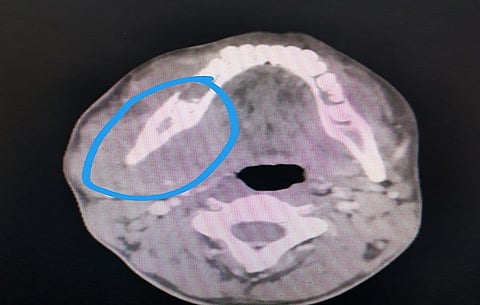

وأكّدت نتائج الأشعة المقطعية مع استخدام الصبغة الوريدية، وجود كتل ورمية في الرقبة اليمنى ومنطقة الزاوية السفلية اليسرى وكذلك في الجيب الفكي الأيسر، مع امتداد الإصابة إلى الصفيحة الجناحية. وبناءً عليه، أُجريت بشكل عاجل خزعة جراحية تحت التخدير الموضعي من منطقتي الفك السفلي الأيمن واللثة، وأكد تقرير قسم الأنسجة إصابة المريض بورم ليمفاوي من نوع بوركيت.